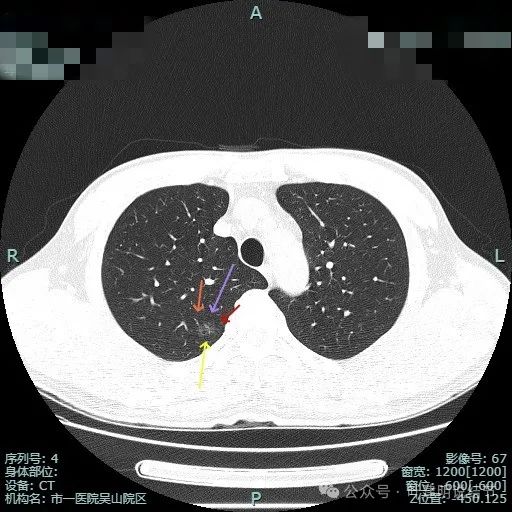

这种混合密度影像像浸润的结节缘何病理仍是原位癌伴微浸润?是否藏着混合磨玻璃结节是原位癌的奥秘!

病史摘要:69 岁男性患者,主因体检发现左肺部占位 2 年余就诊。2 年余前当地医院体检胸部 CT 提示左肺结节,当时有咳嗽咳痰,为白色粘痰,无其他不适,当地医院建议复查。2 年来症状同前,2024 年 12 月 3 日复查胸部 CT 提示左肺上叶部分实性小结节,考虑 MIA 或 IAC,现无明显不适,为求手术治疗入院。诊疗过程:体格检查未提及。辅助检查胸部 CT 提示相关结节情况

原位癌